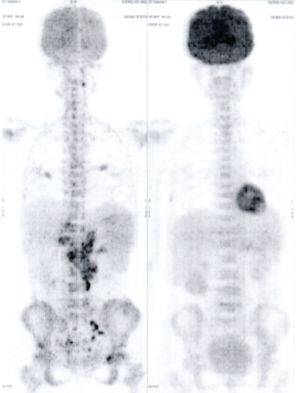

CASE NO: 3 (PROSTATE CANCER)

A middle-aged man with castration resistant prostate cancer, having failed all currently available cancer treatment, was very weak, and getting worse every day. The PET/CT scan showed he had massive bone metastases. After a few treatment, all the bone metastases went into remission. About 6 months later, he is still in remission.

CASE NO: 4 (PROSTATE CANCER)

A middle-aged man with castration resistant prostate cancer and massive bone metastases, failed all currently available cancer treatment, including with the new and expensive drug XTANDI. After a few treatment, most of the bone metastases went into remission, and the remaining ones are less active. Treatment will continue. Cases no: 3 and 4 show that terminal prostate cancer today can be cured with our new cancer treatment.